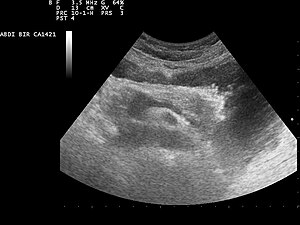

Ультразвуковое изображение поджелудочной железы